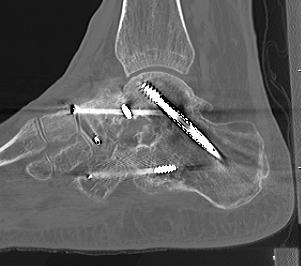

CT

Subluxation of TNJ with advanced STJ OA

TNJ OA with posterior / medial / anterior facet OA of the subtalar joint

Fixation

- 6.5 mm/ 8.0 mm cannulated screw

- inferior calcaneum into body and neck of talus / talus to calcaneum